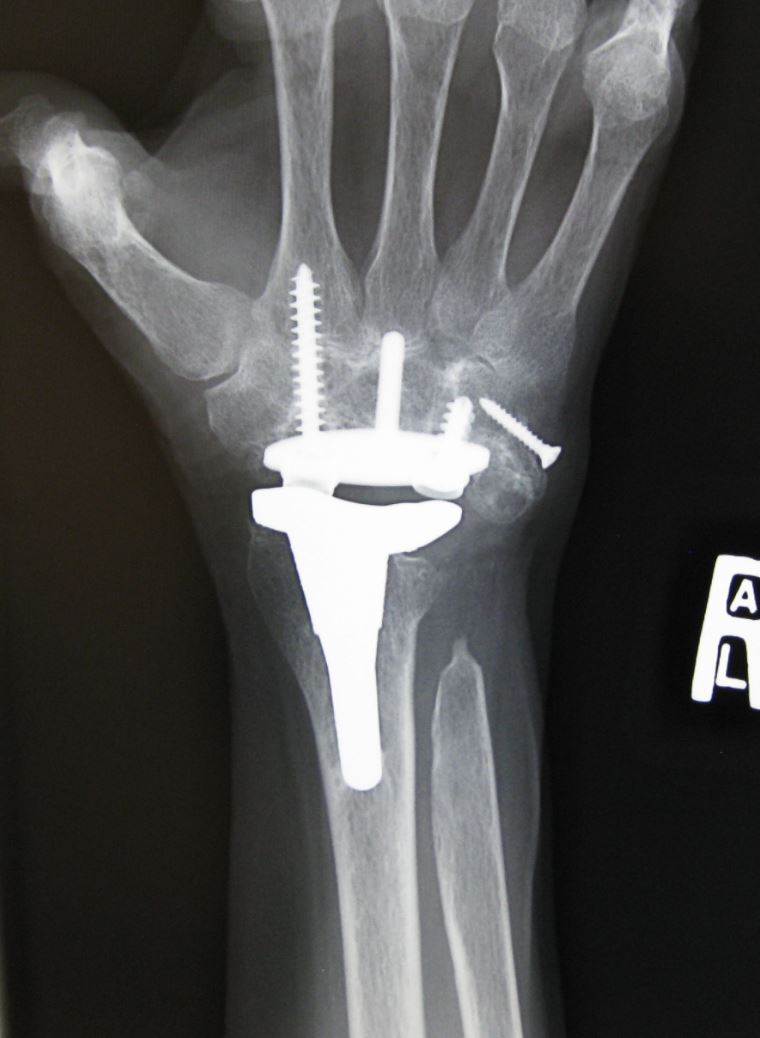

X-ray of Wrist After Joint Replacement

In this total wrist replacement, the damaged bones have been replaced with an implant made of metal and plastic.